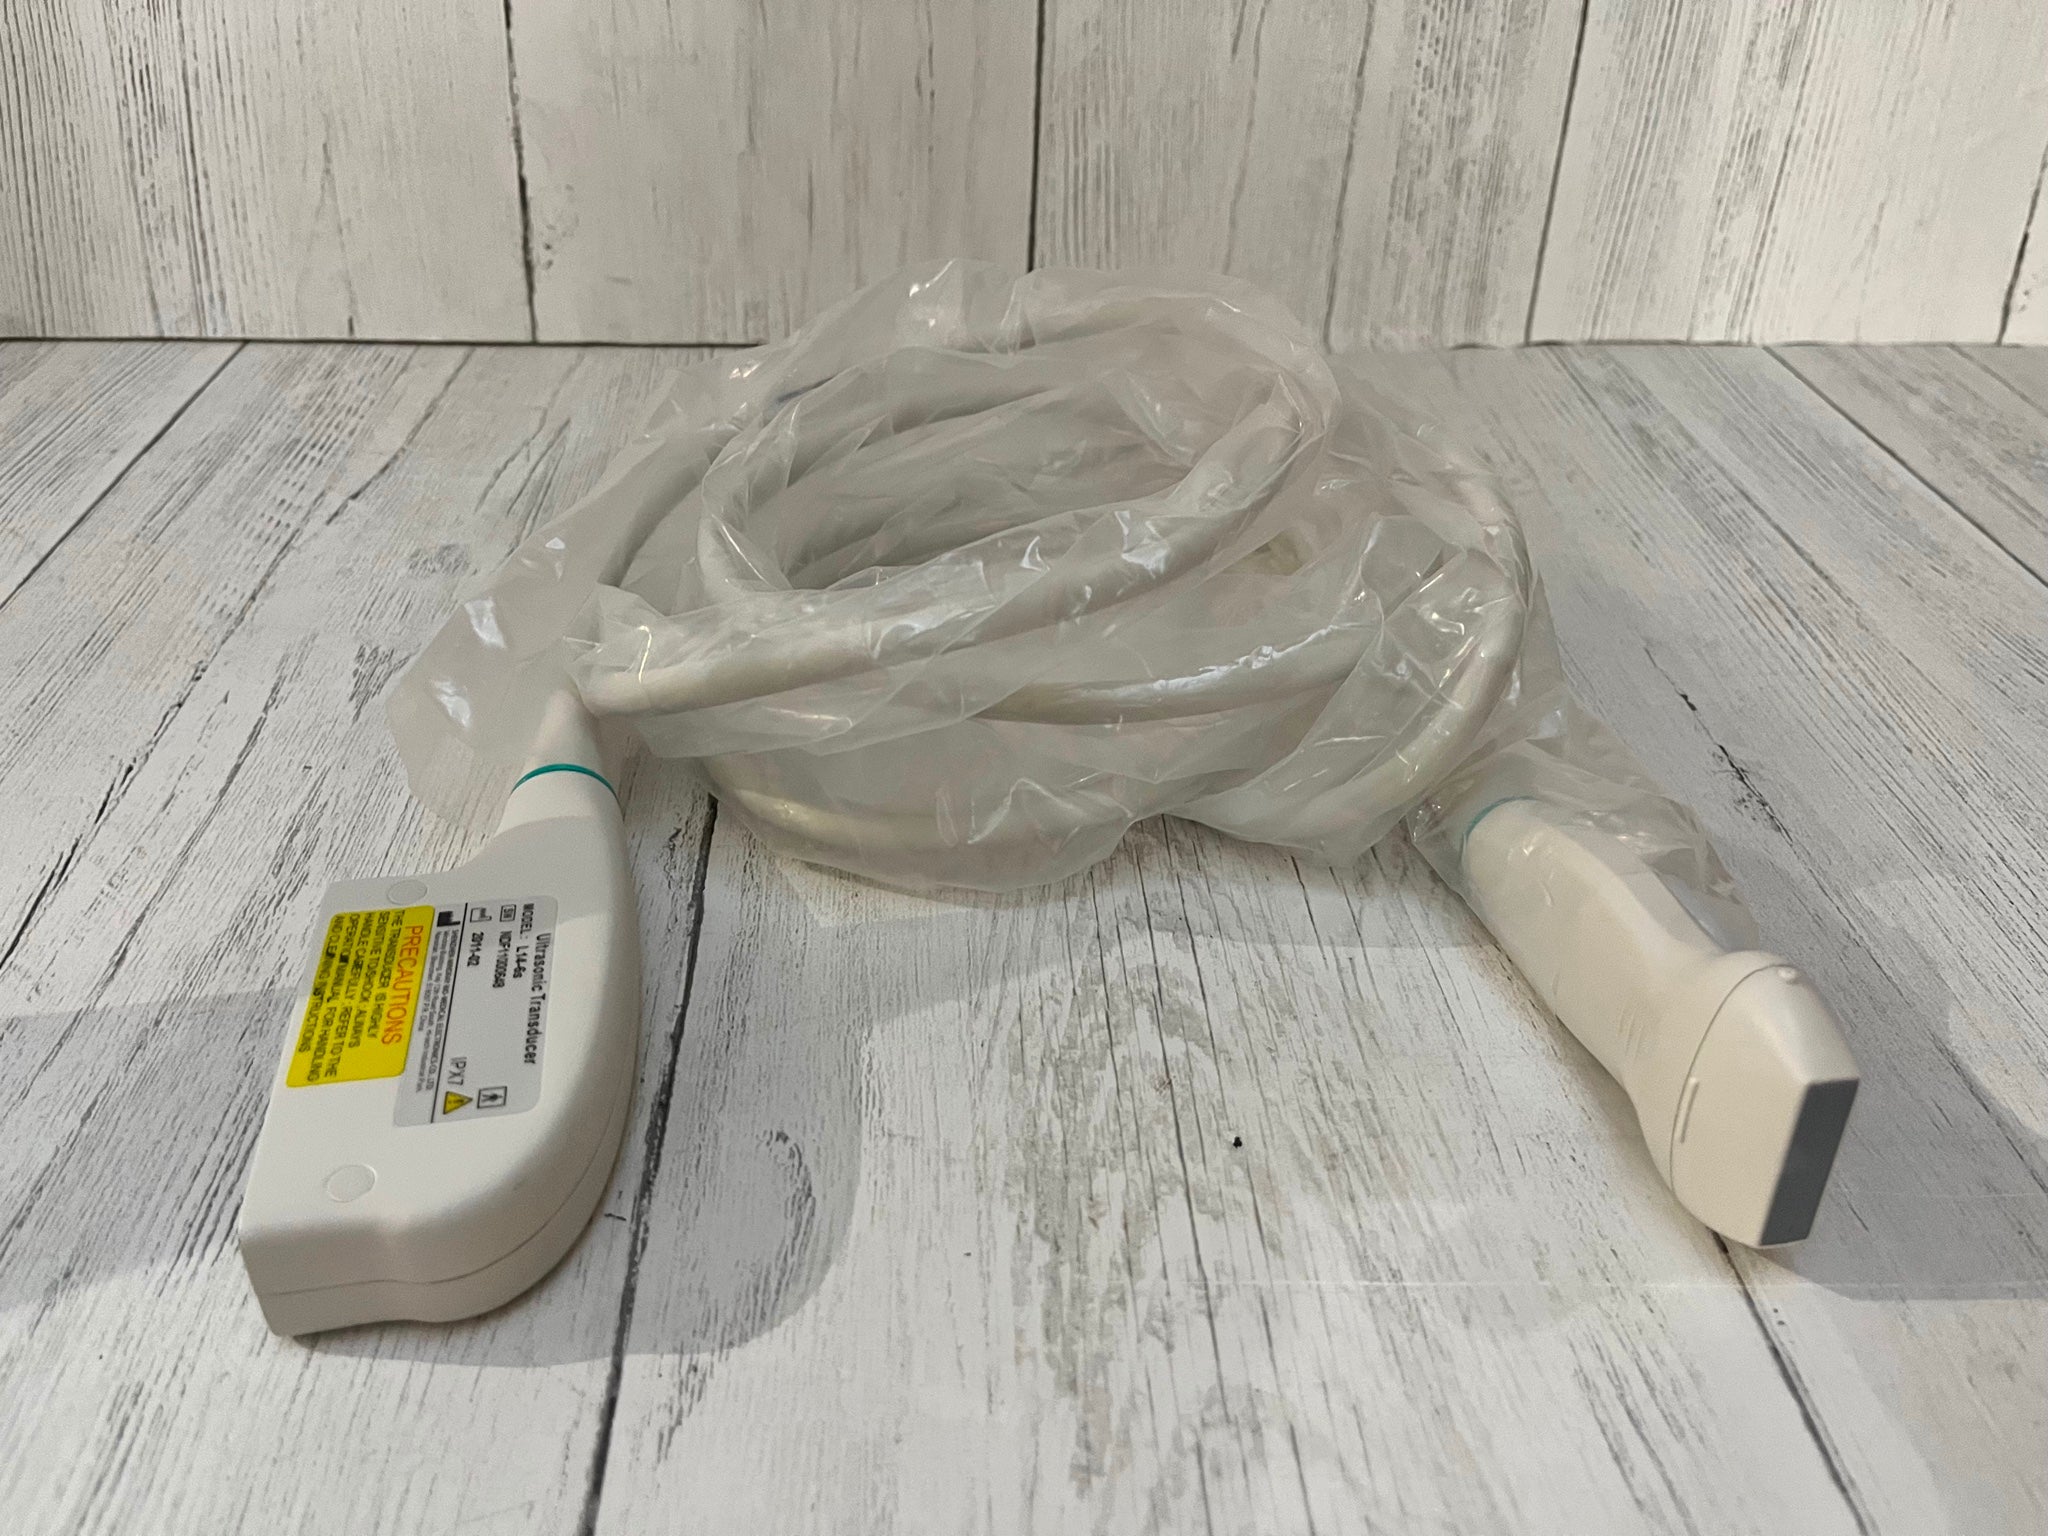

Sonde convexe |